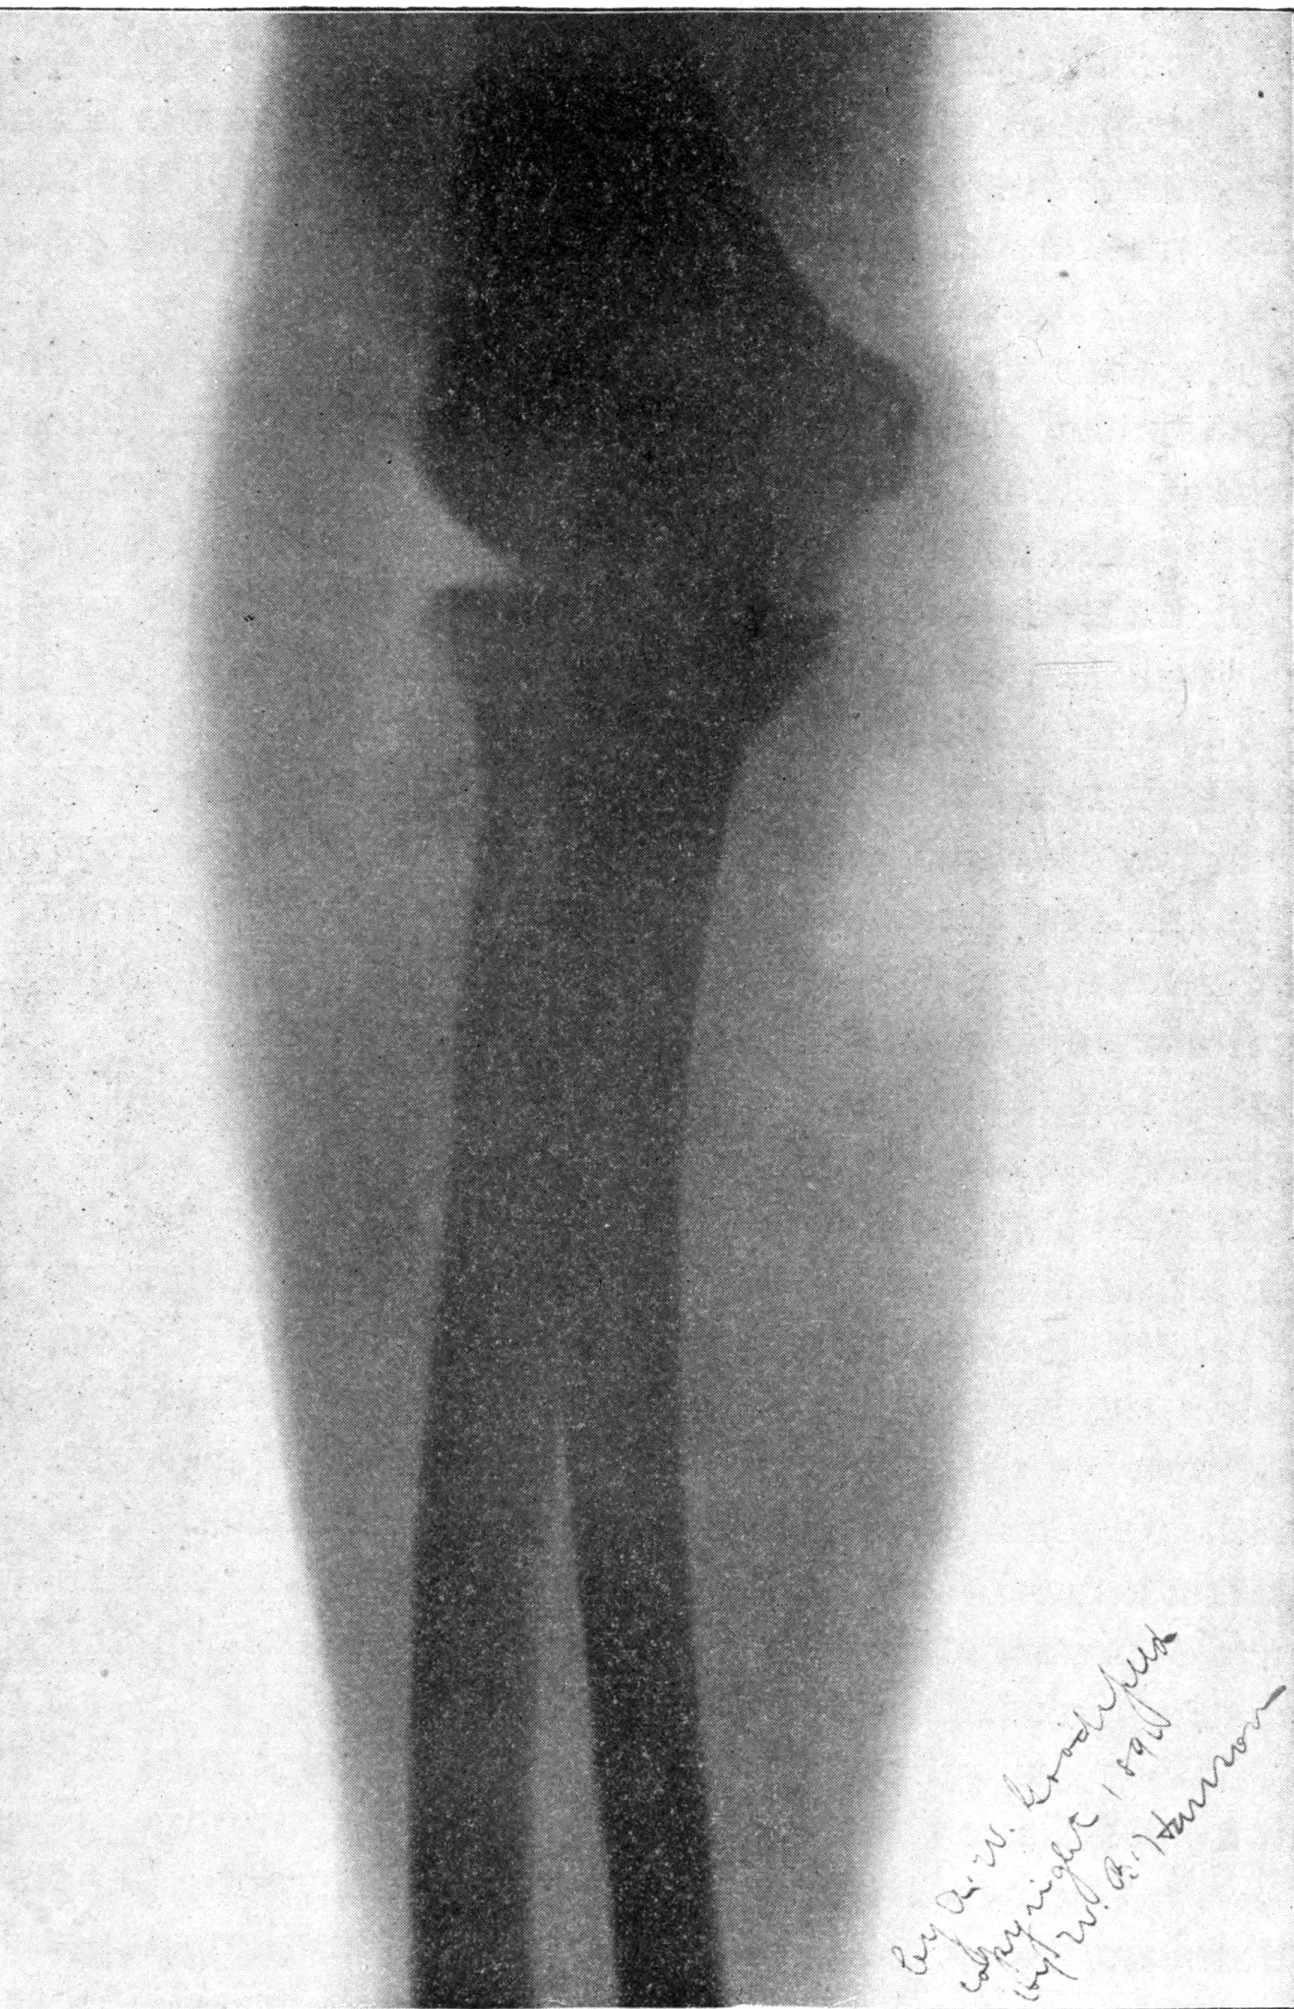

Fig. 2.—Broken Arm, Overlapping.

(Due to defective setting.)

FROM SCIAGRAPHS BY PROF. DAYTON C. MILLER. § 204.